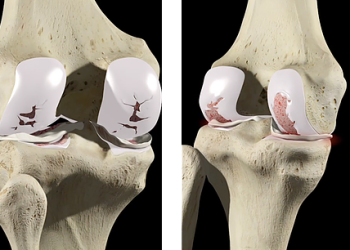

Uma promessa que já tem história: o gel alemão e a corrida pela regeneração da cartilagem

Na medicina, não é raro que uma inovação celebrada como inédita traga, na verdade, ecos de pesquisas anteriores. Foi o...